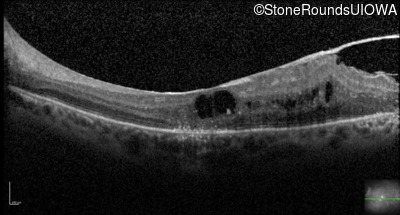

Optical Coherence Tomography - Left - 20/160

Exemplar / OCT Stack